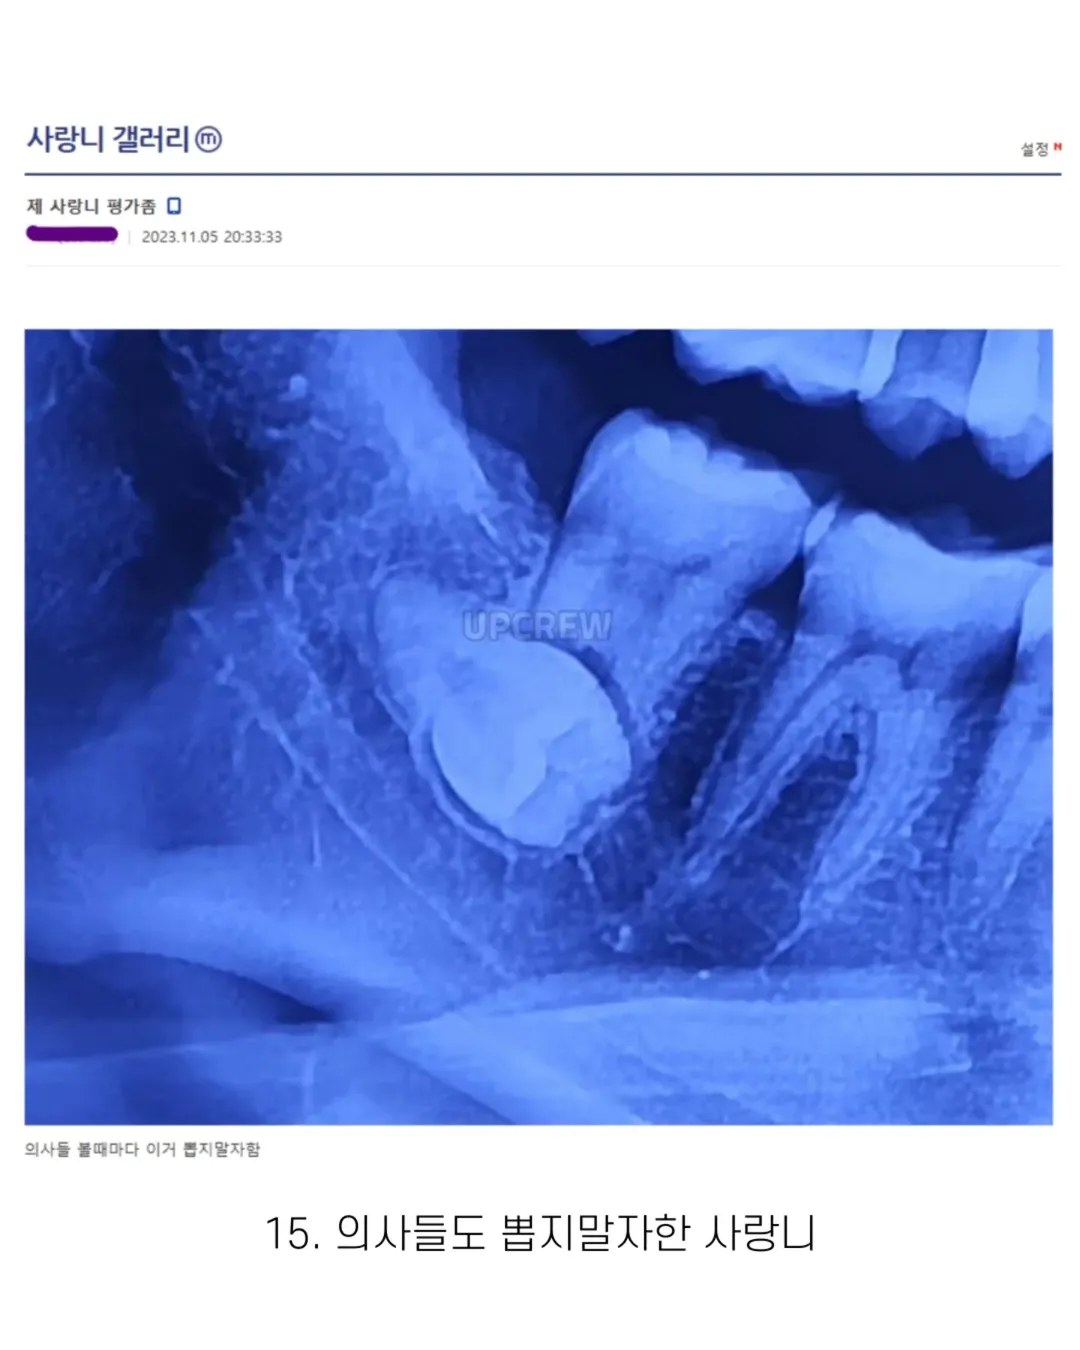

사랑니 갤러리의 특이한 사랑니들 (약혐 주의)

위치가 애매한데 저 위에 잇는 거랑 같이 빼야되거나 아니면 저 치아 앞에 있는 거면 뼈 싹 갈아서 열어야될 거 같어

익인6

빼는 게 더 위험해보여